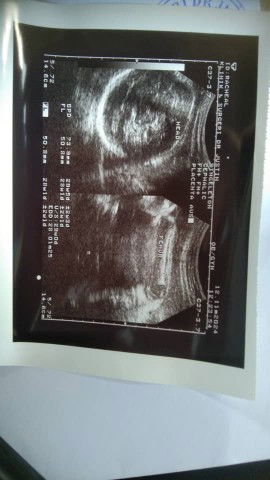

Haii mmy smua nk tnya korng tngk nii girl or boy

Sorry tak reti tengok 😅 Doktor takde bagi tahu awak ke?